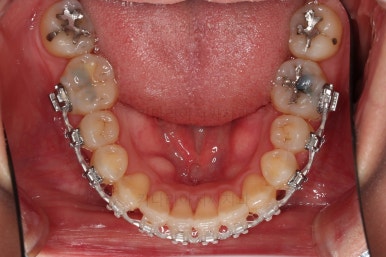

초진 시, 입안의 모습입니다.

좌측 송곳니가 덧니처럼 튀어나가 있고, 송곳니 옆의 작은 억므니가 안으로 쏙 들어가서 덧니 느낌이 더 강조되어 보이네요.

위아래 앞니가 긴밀하게 겹침이 없는 약간의 개방교합(오픈바이트, Openbite) 경향이 보입니다.

이번에 선택하신 장치는 자가결찰 세라믹 중에 엠파워 클리어라는 장치인데요.

흔히들 아시는 클리피씨도 같은 분류의 장치입니다.

철사가 들어가니 삐뚤한 치열이 더 강조되어 보이네요.